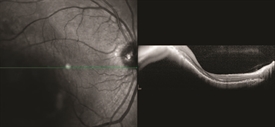

Figure 1. OCT analysis of macular choroidal melanoma medium. Photo credit: Timothy G. Murray, MD, MBA

During a targeted tumor examination, diagnostic testing typically includes a complete eye exam with dilation of the fundus, indirect ophthalmoscopy, tumor photography (fundus photography), tumor ultrasound, and vascular studies of the tumor (fluorescein angiography, indocyanine green angiography, spectral-domain OCT angiography (sd OCT)), along with laser studies of the macula. These imaging studies evaluate the tumor, allowing documentation of the clinical diagnosis. (See Clinical Terms section for other related screenings.) The ocular tumor is then staged—a process that defines the extent of tumor based on its length, width, and height.